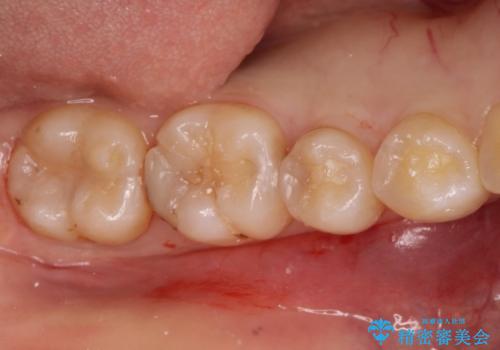

自然な見た目のセラミックインレー

- むし歯の治療を希望されて来院された患者様です。

セラミックインレーによる修復を行っております。

自然な見た目に満足して頂きました。

保険治療で使える材料には制限があり、見た目だけでなく精度でも劣ります。当院でのセラミックインレーは歯とのつなぎ目を拡大鏡で確認して精度高く仕上げるため、むし歯のリスクを限りなく少なくできるよう治療します。